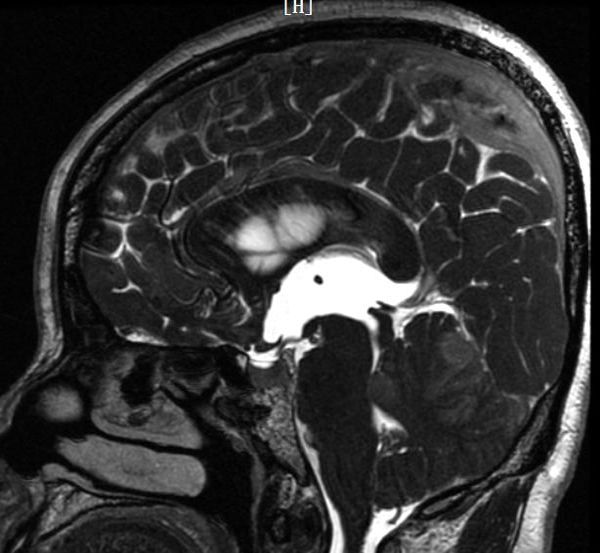

3月4日,陕西省核工业二一五医院神经外科重症监护室首次应用最小备皮法成功为一位39岁的女性患者实施脑室镜下三脑室底造瘘术。患者张女士近来频频头痛头晕,影响到了正常工作生活,经头颅MRI检查提示,“幕上脑室系统扩大,双侧脑室额角周围间质水肿”。磁共振3D FIESTA序列检查,可见三脑室、侧脑室扩大明显,中脑导水管下口阻塞、三脑室底受压下陷,诊断为梗阻性脑积水,毫无疑问需要手术治疗。

按照常规术前准备,首先需要“剃光头”。但作为一名女性理发师,头发对张女士的重要程度可想而知。了解情况后,神经外科肖三潮主任组织科室讨论,制定了脑室镜微创治疗方案,从备皮部位、范围、程度及术前准备、术中操作、术后管理等多个环节制定计划。3月4日,由神经外科重症监护室谢国强主任、肖学谦副主任医师在脑室镜监视下,顺利实施脑室镜下三脑室造瘘术及侧脑室内脉络丛电灼术。手术切口位于右侧额部,长约4cm,颅骨钻孔直径只有1cm大小。